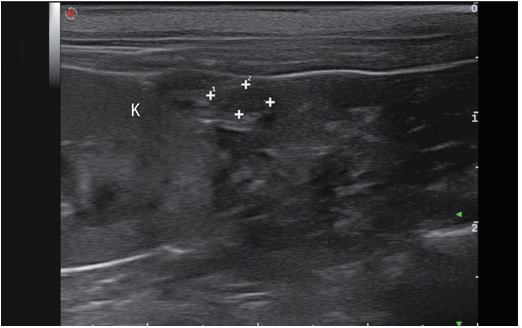

雌性生殖系统可按从尾侧到头侧的顺序进行扫查,从位于后腹部,膀胱和降结肠之间的子宫体开始扫查。跟踪子宫角向头侧行走可见卵巢。或者在两侧肾脏尾极的后方直接寻找卵巢。

卵巢位于肾脏尾极的外侧,为一圆形或椭圆形的结构,长度小于1cm(图4)。其影像表现与当时所处发情周期有关。使用高频探头可以对无回声的亚毫米级的原始卵泡进行评估(图5),它们通常位于卵巢的外缘(卵巢皮质层含有卵泡,而卵巢髓质内含有血管和神经)。